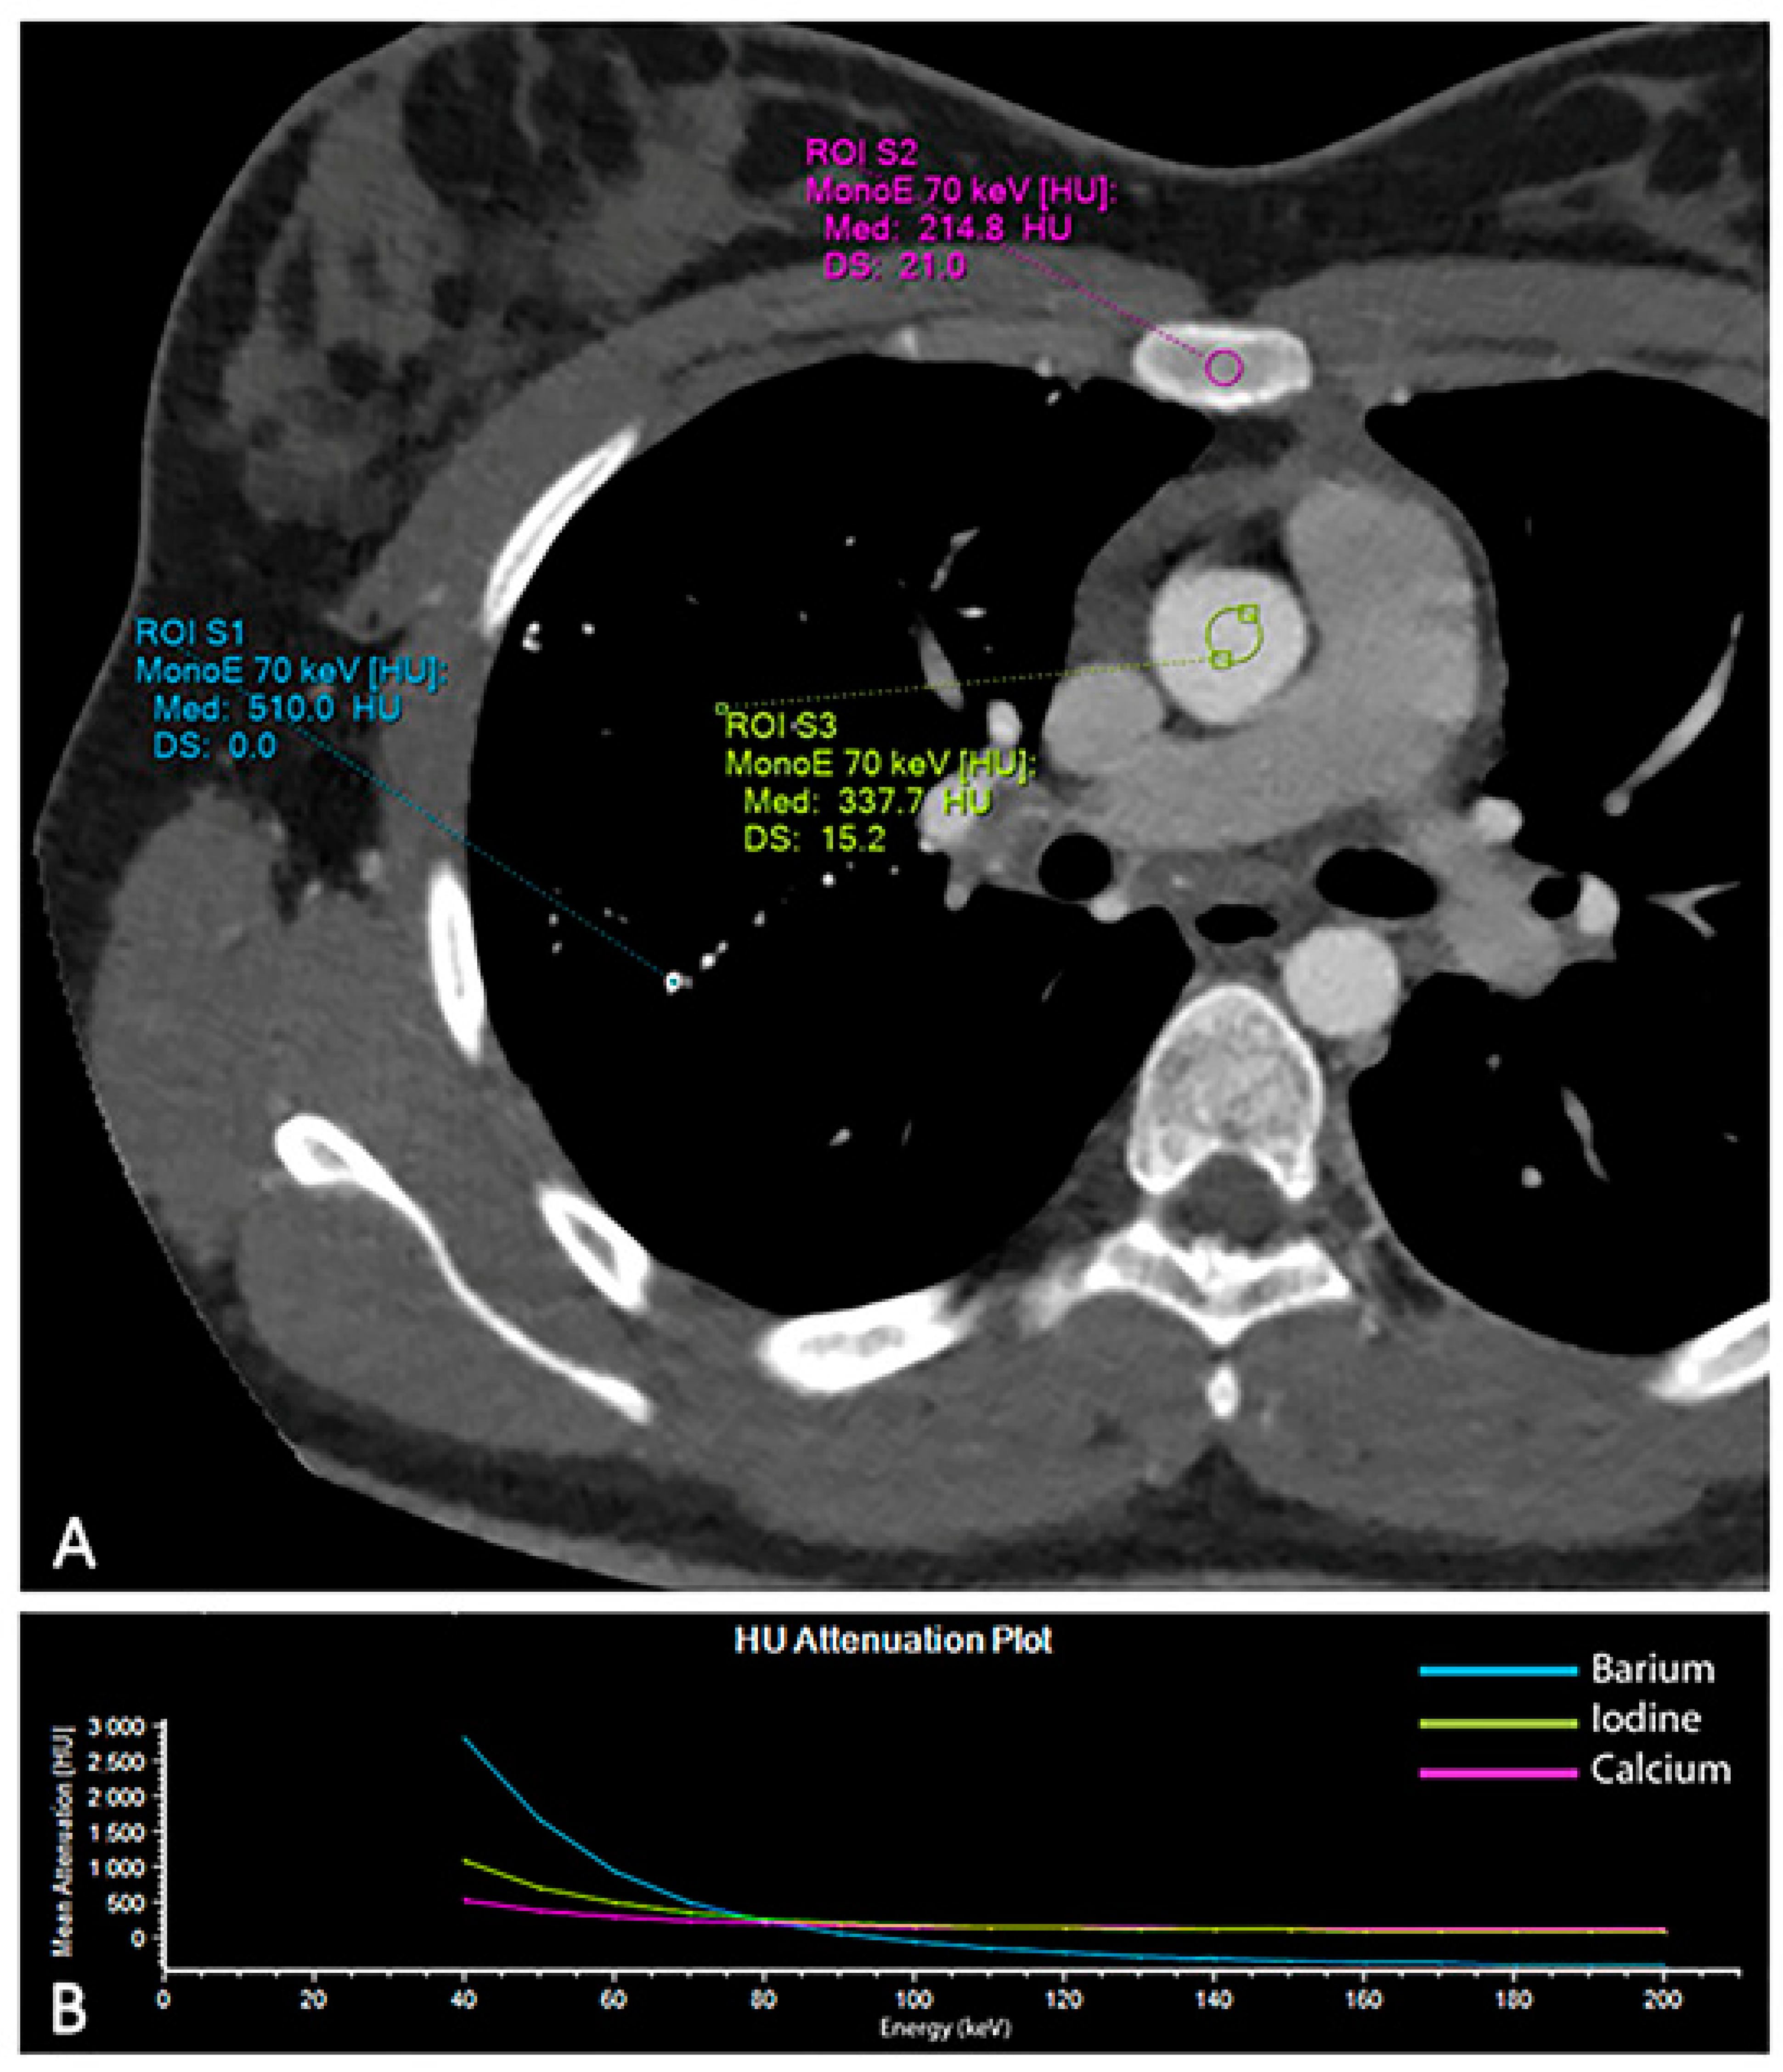

2. Case Report